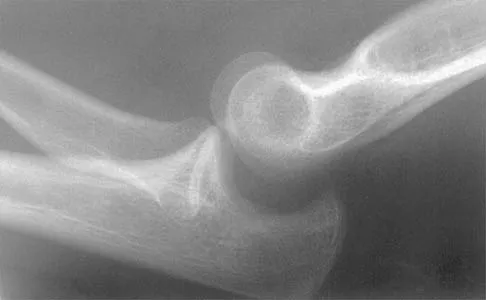

Figure 27 shows the radiograph of a 26-year-old man who sustained a closed head injury and a closed elbow dislocation 6 weeks ago. Examination reveals 65 degrees to 115 degrees of flexion, and intensive physical therapy has resulted in no improvement. A decision regarding the timing of surgical correction of the contracture should be based on

Explanation

The patient has heterotopic ossification, a more common finding in patients who have sustained head injuries. Treatment will require removal of the heterotopic bone and anterior and posterior capsulectomies. The main concern about timing is the possible recurrence of heterotopic bone. While an extended wait was once thought necessary, this is no longer true. The timing is based on the time since injury and evidence of bone maturation on plain radiographs. A sharp marginal demarcation of the new bone and a trabecular pattern within it are usually present 3 to 6 months after onset, indicating that it is safe to proceed with surgical excision. It is not necessary to wait more than 6 months. Bone scan results are not good indicators because they may remain "hot" for long periods of time. The levels of alkaline phosphatase and serum calcium-phosphorus product do not need to be measured.